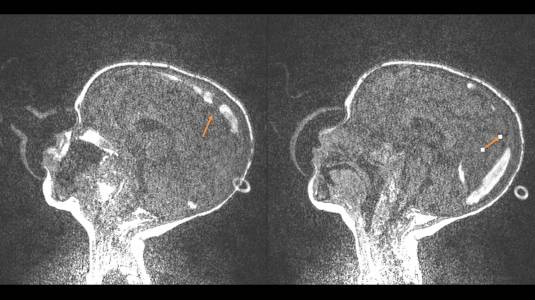

Paciente foi avaliado e indicado tratamento com anticoagulação utilizando enoxaparina em dose plena. O paciente apresentou piora progressiva dos sintomas, chegando a apresentar hemiplegia a esquerda. Nova ressonância é solicitada demonstrando piora da trombose.

Foi realizada discussão entre as diversas especialidades, em vista da não melhora com o uso do anticoagulante, foi sugerido a tentativa de trombectomia mecânica do seio dural.